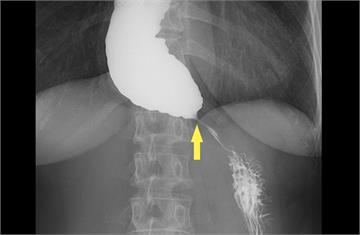

{PLAYICON}她一吃東西就胸悶竟是罕病! 「鳥嘴狀食道」卡住食物